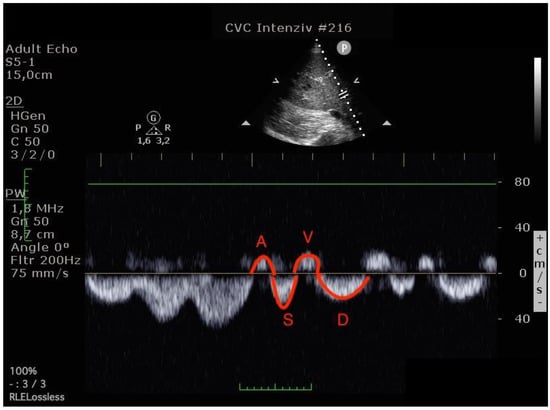

Blood flow was measured in the common hepatic vein right before draining into the inferior vena cava using pulse-waved Doppler ultrasound. The normal hepatic vein waveform has four components: a retrograde A, an anterograde S, a transitional V (which may be anterograde, retrograde, or neutral), and an anterograde D wave [,]. (Figure 2) We recorded the maximal velocities and velocity-time integrals (VTI) of the standard four waves (A, S, V, D) [,] (Figure 3 and Figure 4). The baseline ratios of the retrograde and anterograde waves were calculated preoperatively and their change in the postoperative measurement (20–24 h after surgery), is expressed as a delta ratio. The ratios of retrograde to anterograde VTIs were also calculated.

Figure 3.

Hepatic venous flow pattern (The left image was done before operation, the right image in the postoperative 24th hour. On the postoperative image, A and V waves appear increased, while the S wave is smaller than the D wave. (A VTI: 6.47 to 8.29, S VTI: 12.31 to 8.12, V VTI: 5.98 to 7.98 and D VTI: 11.12 to 9.39).